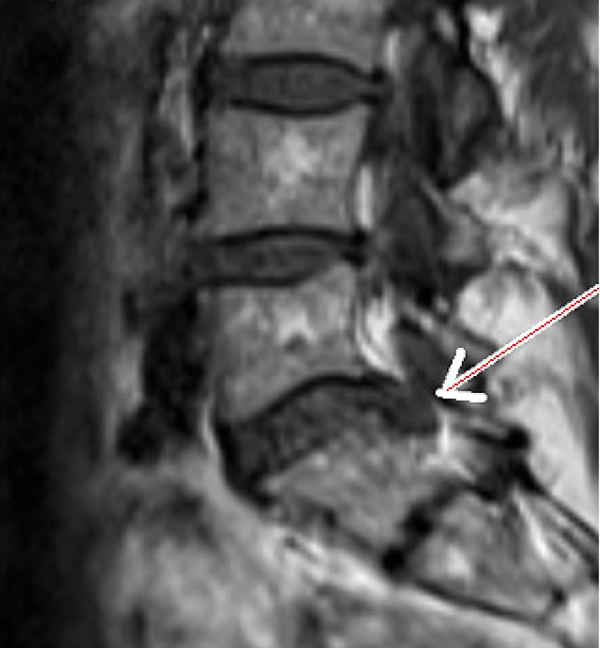

Die folgenden MRT Bilder stammen von einem Patienten mit Bandscheibenvorfall L5/S1. Der Patient ist vorher mehrere Monate arbeitsunfähig gewesen und wurde mit diversen konventionellen Verfahren erfolglos behandelt. Als nächster Schritt wäre eine OP angestanden, die mit der SpineMED® Therapie verhindert werden konnte. Sollten Sie Fragen haben, zögern Sie nicht uns zu kontaktieren, wir bemühen uns um einen Zeitnahen Termin für Sie, und beantworten alle Fragen gerne.

Nach Spinemed